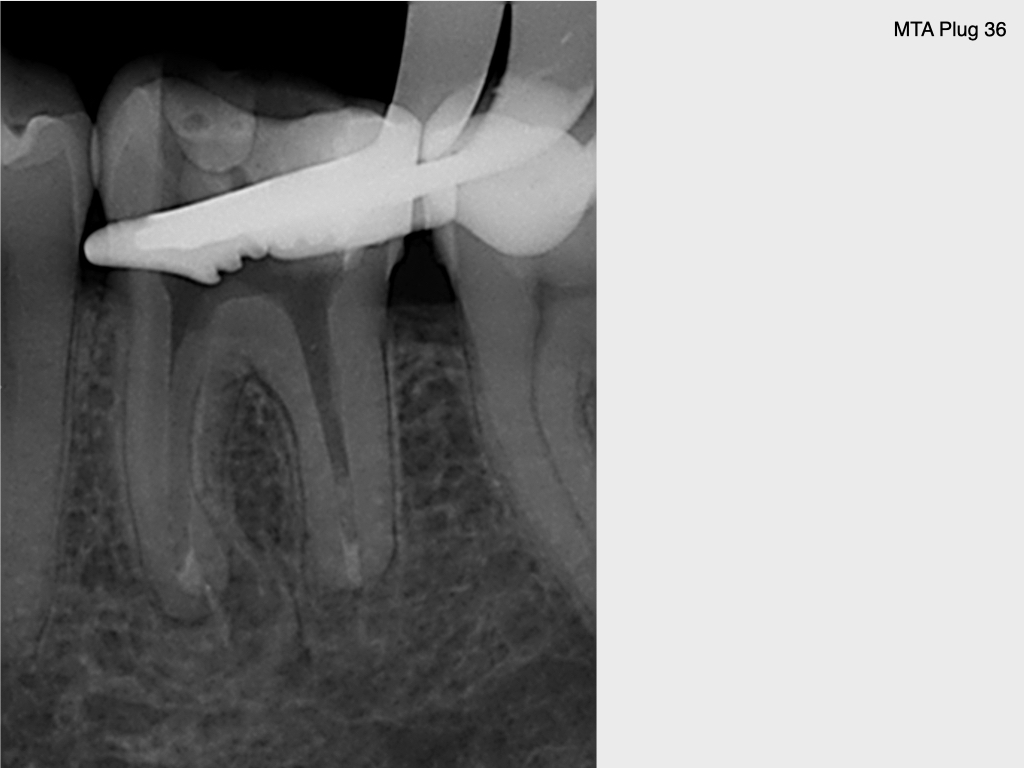

10 Jahres Recall